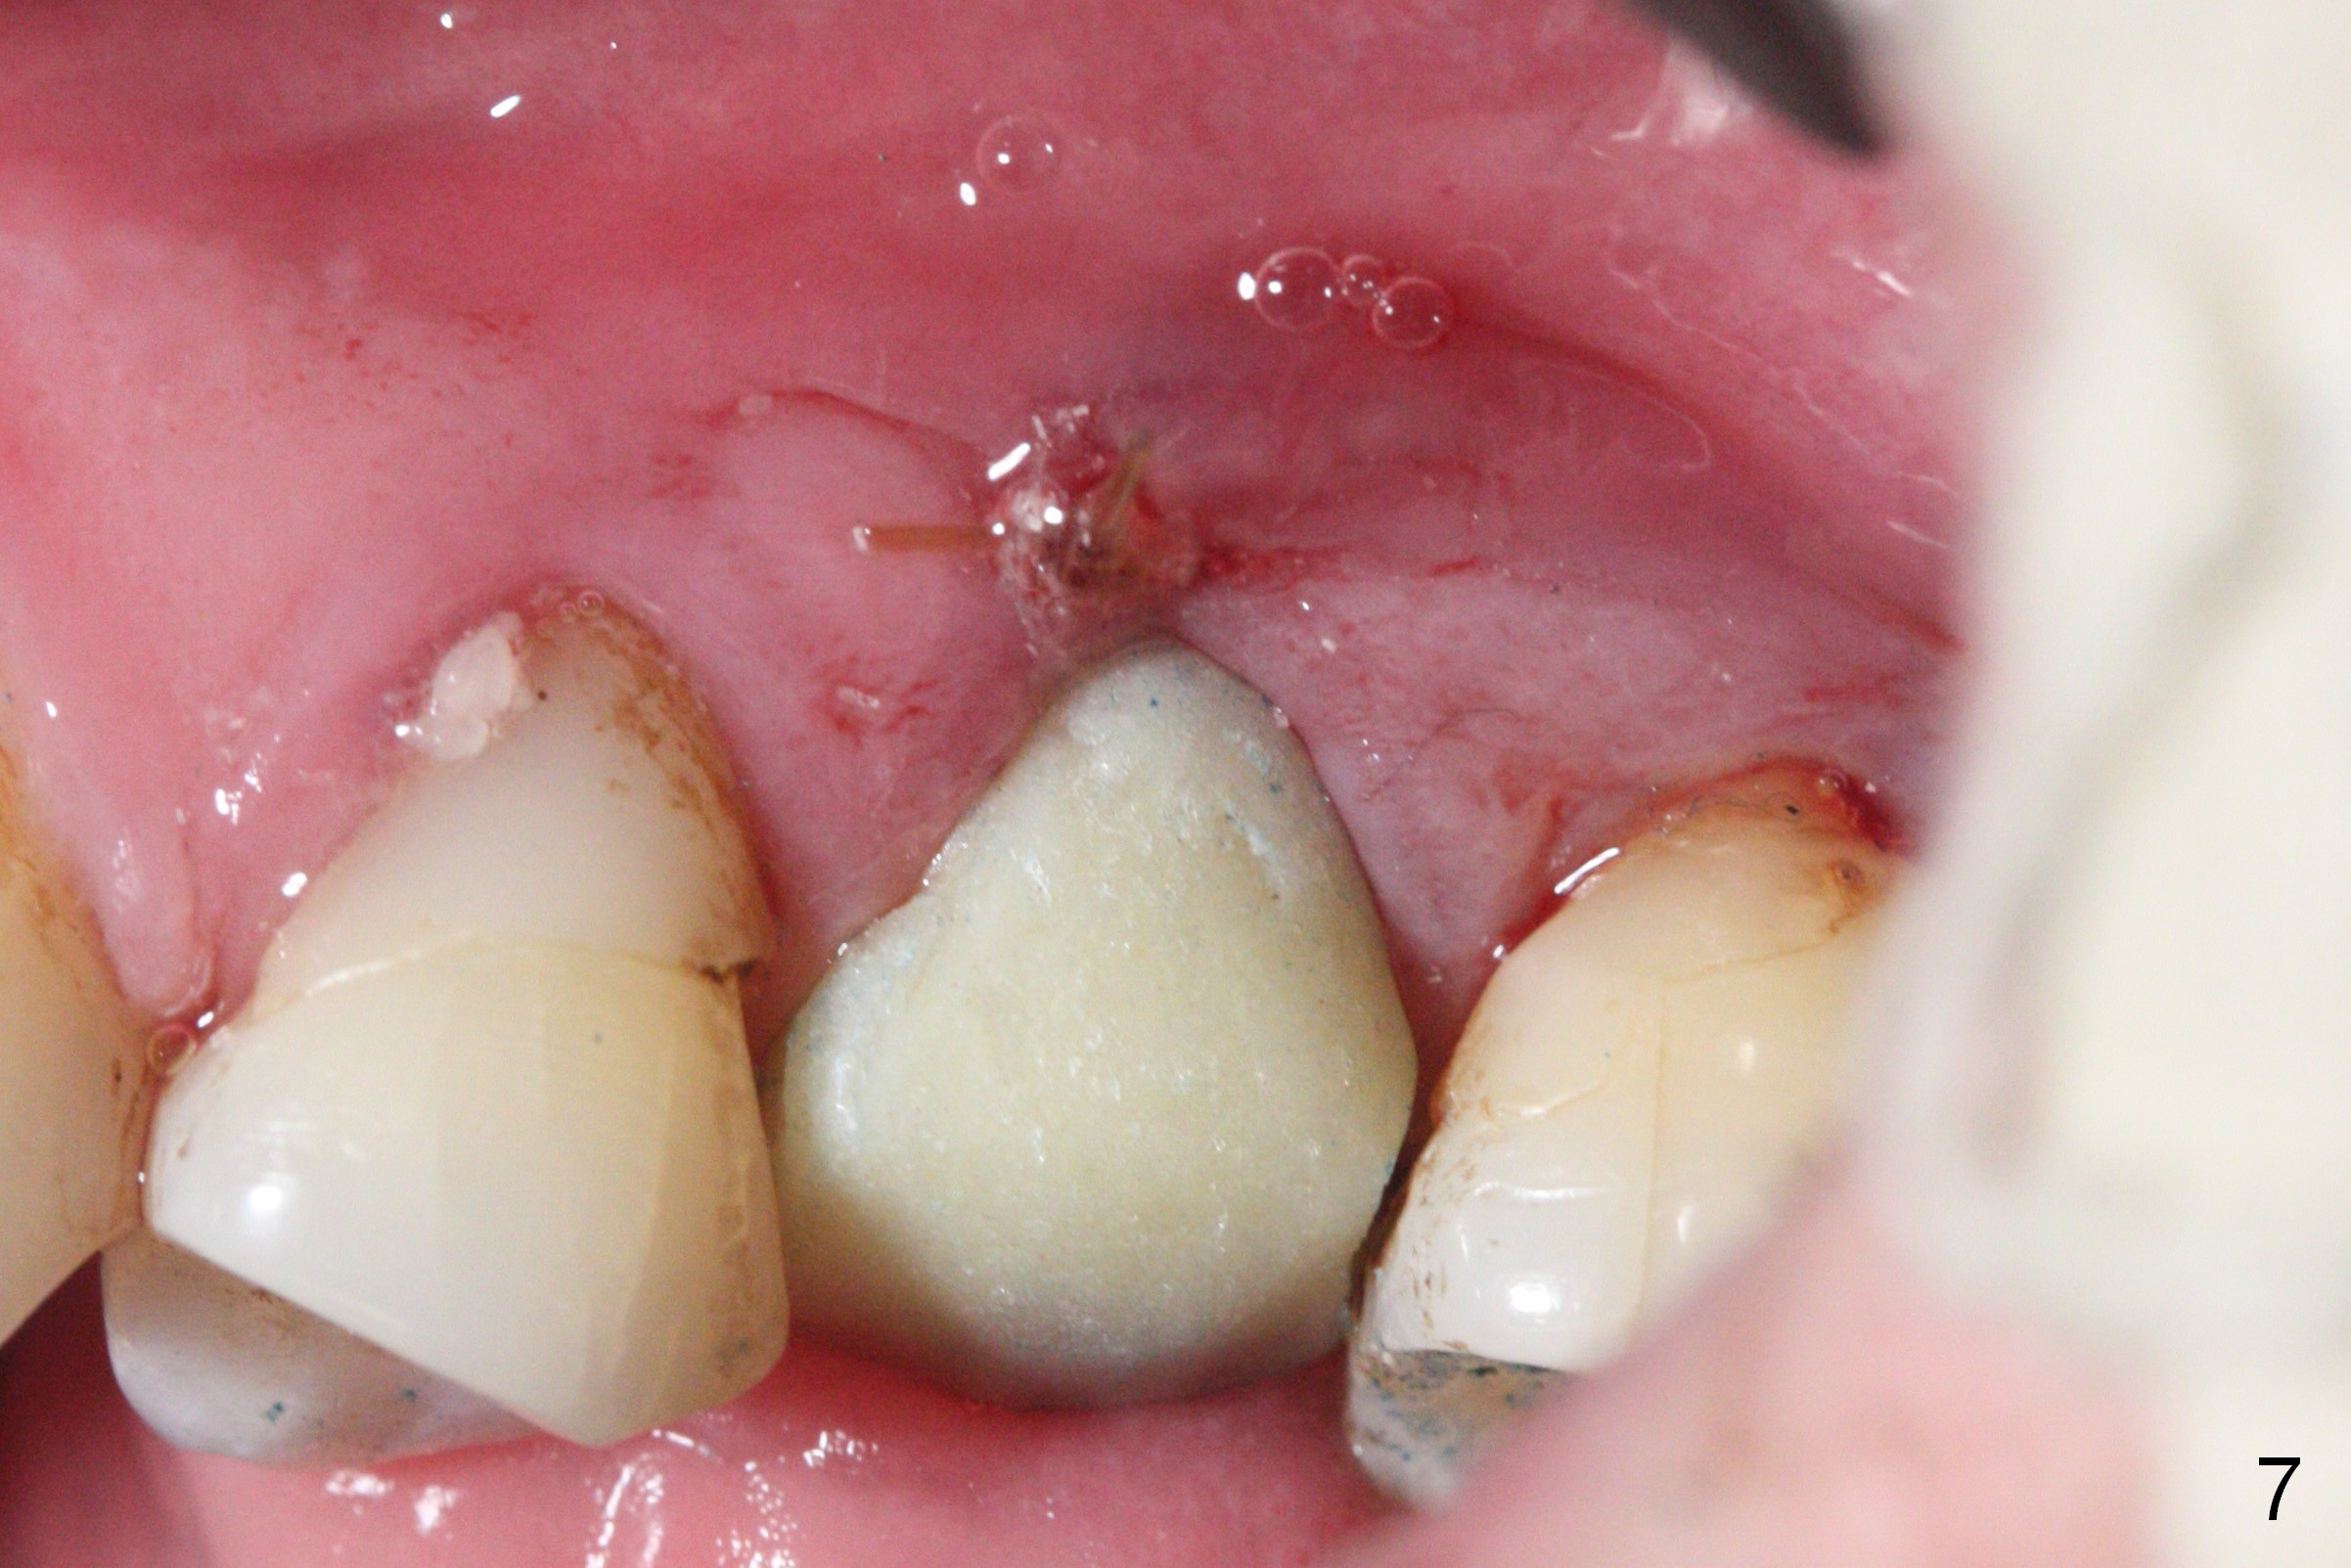

Initial osteotomy depth is 18 mm (Fig.1 green line) with 9 mm in the native bone (red line). The bone density feels to be low. There is at least 2 more mm bone apically (pink line). The depth is increased by 2 mm so that when a 3.8x15 mm implant is placed, there is 10-11 mm implant/bone contact (Fig.2 red line). There is large bony defect (Fig.3 *), which is bone grafted (Fig.4 *). Finally a longer abutment is placed (4.5x5.5(5) in Fig.4 vs. 4.5x4(5) in Fig.2,3). The 5 mm cuff does not look too long buccally (Fig.5) or palatally (Fig.6). To prevent postop buccal gingival overgrowth (2), the buccal margin of an immediate provisional is subgingival (Fig.7-9 *). Bone density between #13 and 14 appears to increase 3 months postop (Fig.10). The implant seems to be equi-crestal (Fig.11 ^). There seems to be more bone growth (i.e., decreasing gap) 6 months postop (Fig.12). Impression is taken. A crown is delivered nearly 7 months postop (08/07/2017). While there is minimal bone loss at #13 and 15 three years and 4 months post cementation, the tooth #14 and 18 are mobile (Fig.13,14).